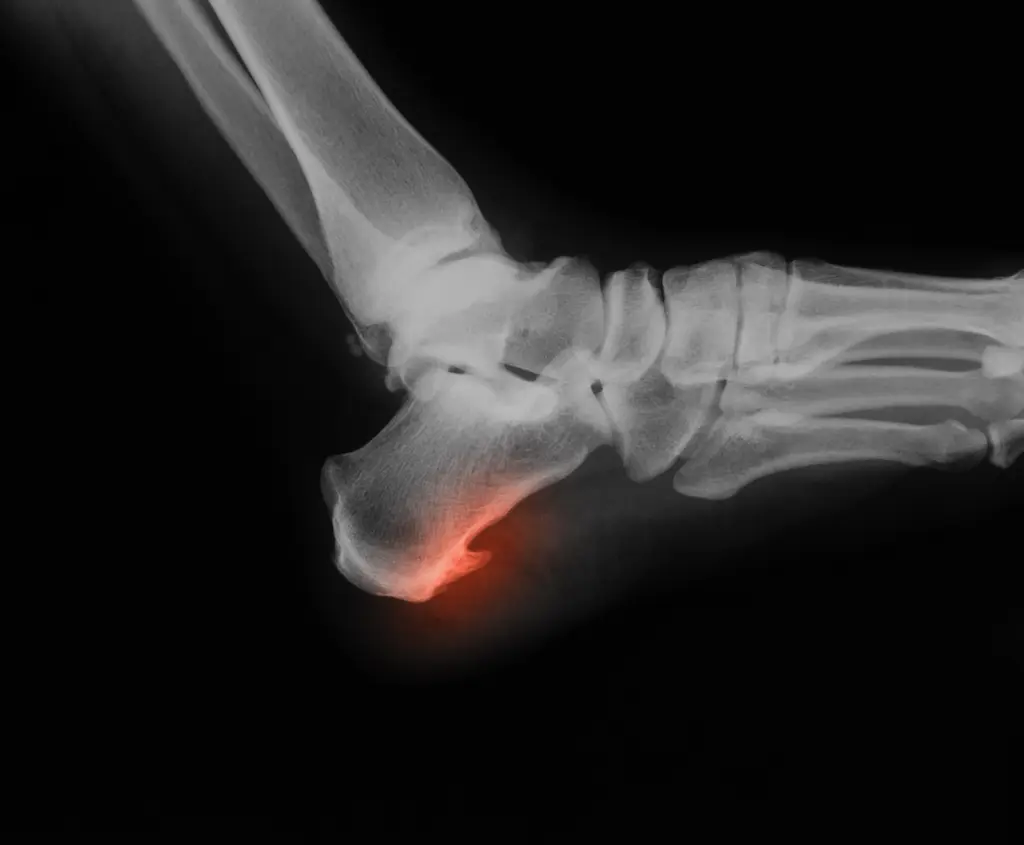

Foot Problems In Seniors . Learn about six common causes of foot pain in older adults, such as stress fractures, plantar fasciitis, psoriatic arthritis, diabetes, gout and nerve damage. One of the most common conditions across all generations is plantar fasciitis, also known as “heel spur. Taking care of your feet and starting treatment early can. Due to changes in your foot structure over time, you are more at risk for developing foot problems as you get older. If you or anyone in your family are experiencing foot problems as you get older, we’re here to. Dry skin, especially on the soles of the feet, is a problem that may require a daily application of moisturizer to prevent cracking and infection. Why choose university foot and ankle institute for family foot care? Plantar fasciitis refers to pain at the bottom of the foot, on the heel and around.